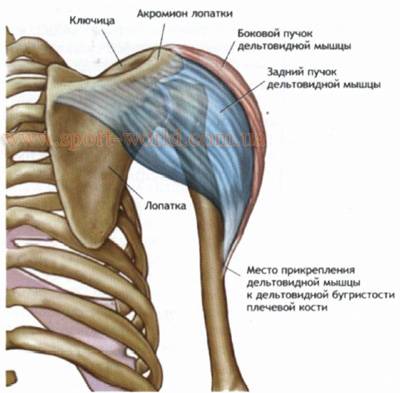

Фотографии поддельтовидной мышцы плечевого сустава